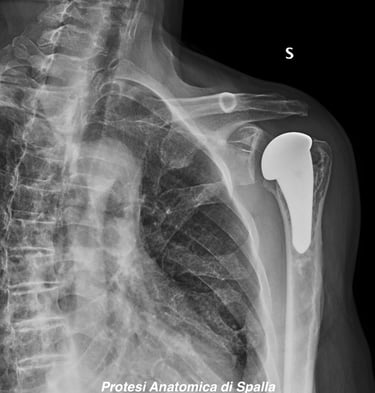

Artrosi di spalla (Gleno-Omerale)

Gallery

Attività Chirurgica